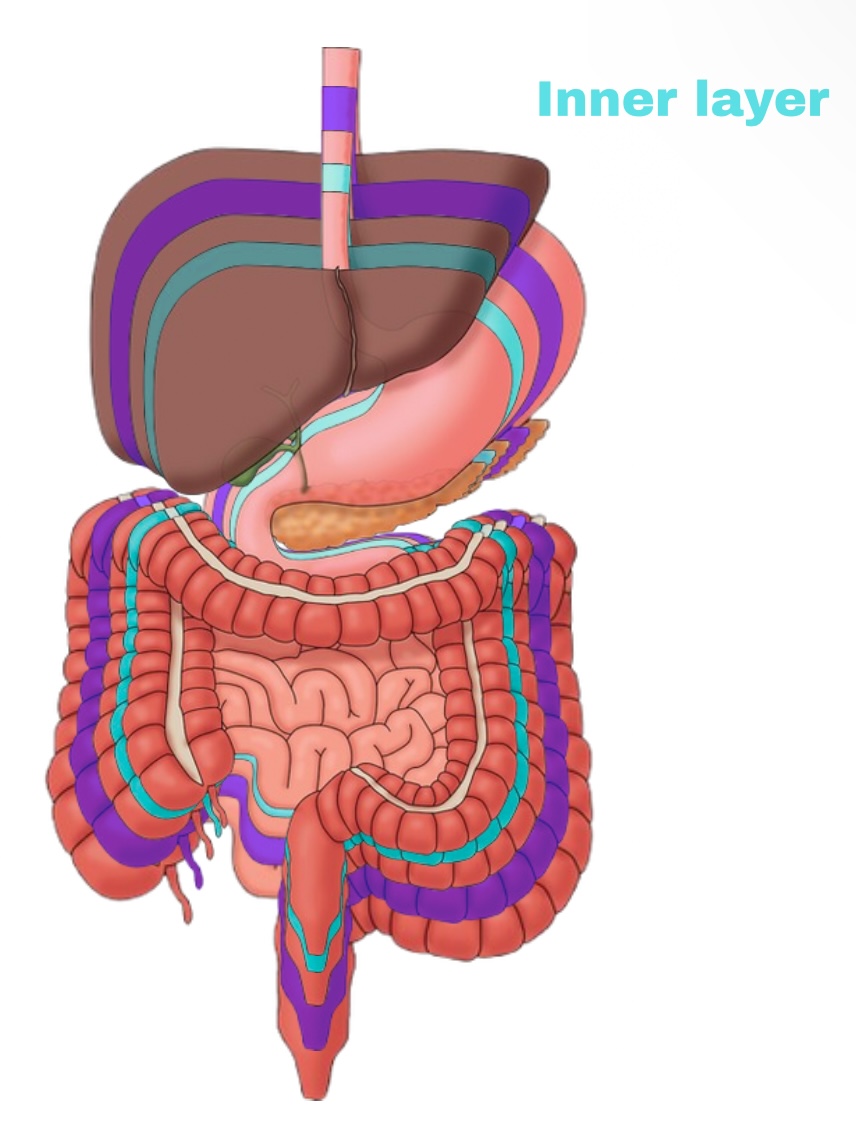

Visceral Peritoneum

Deep layer (surface of organ)